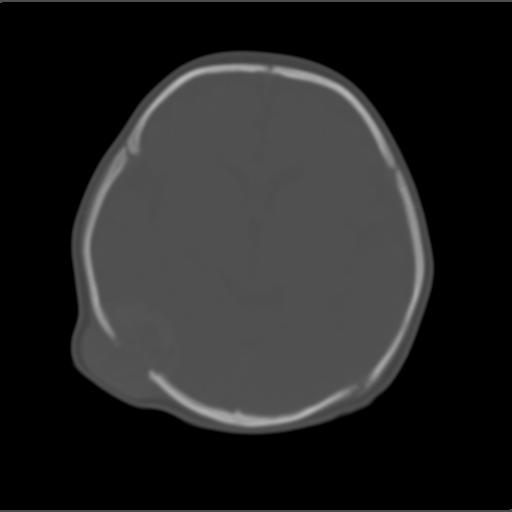

f2m出生已来可见右侧枕部见包块,质地软,无外伤史。包块处ct值16-67hu,大小约3.1x3.2cm左右。

局部颅骨破坏,并以破坏为中心的高密度肿块影,内示软骨影,考虑颅骨软骨瘤.

仔细看颅骨是分离

骨质还算完整。

有无产伤?血肿机化.(颅盖骨是膜化骨,不存在软骨瘤)